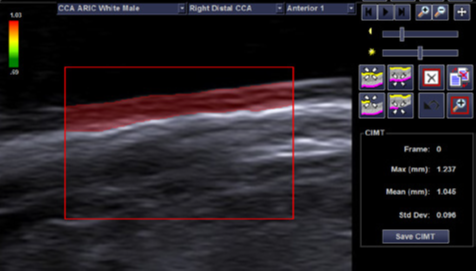

syngo 动脉健康评估软件包选件

- 可用于线阵探头

- 提供一种量化颈总动脉内中膜厚度(CIMT)的方法

- 使用半自动化的边界检测来确定颈总动脉内中膜的最大厚度和平均厚度